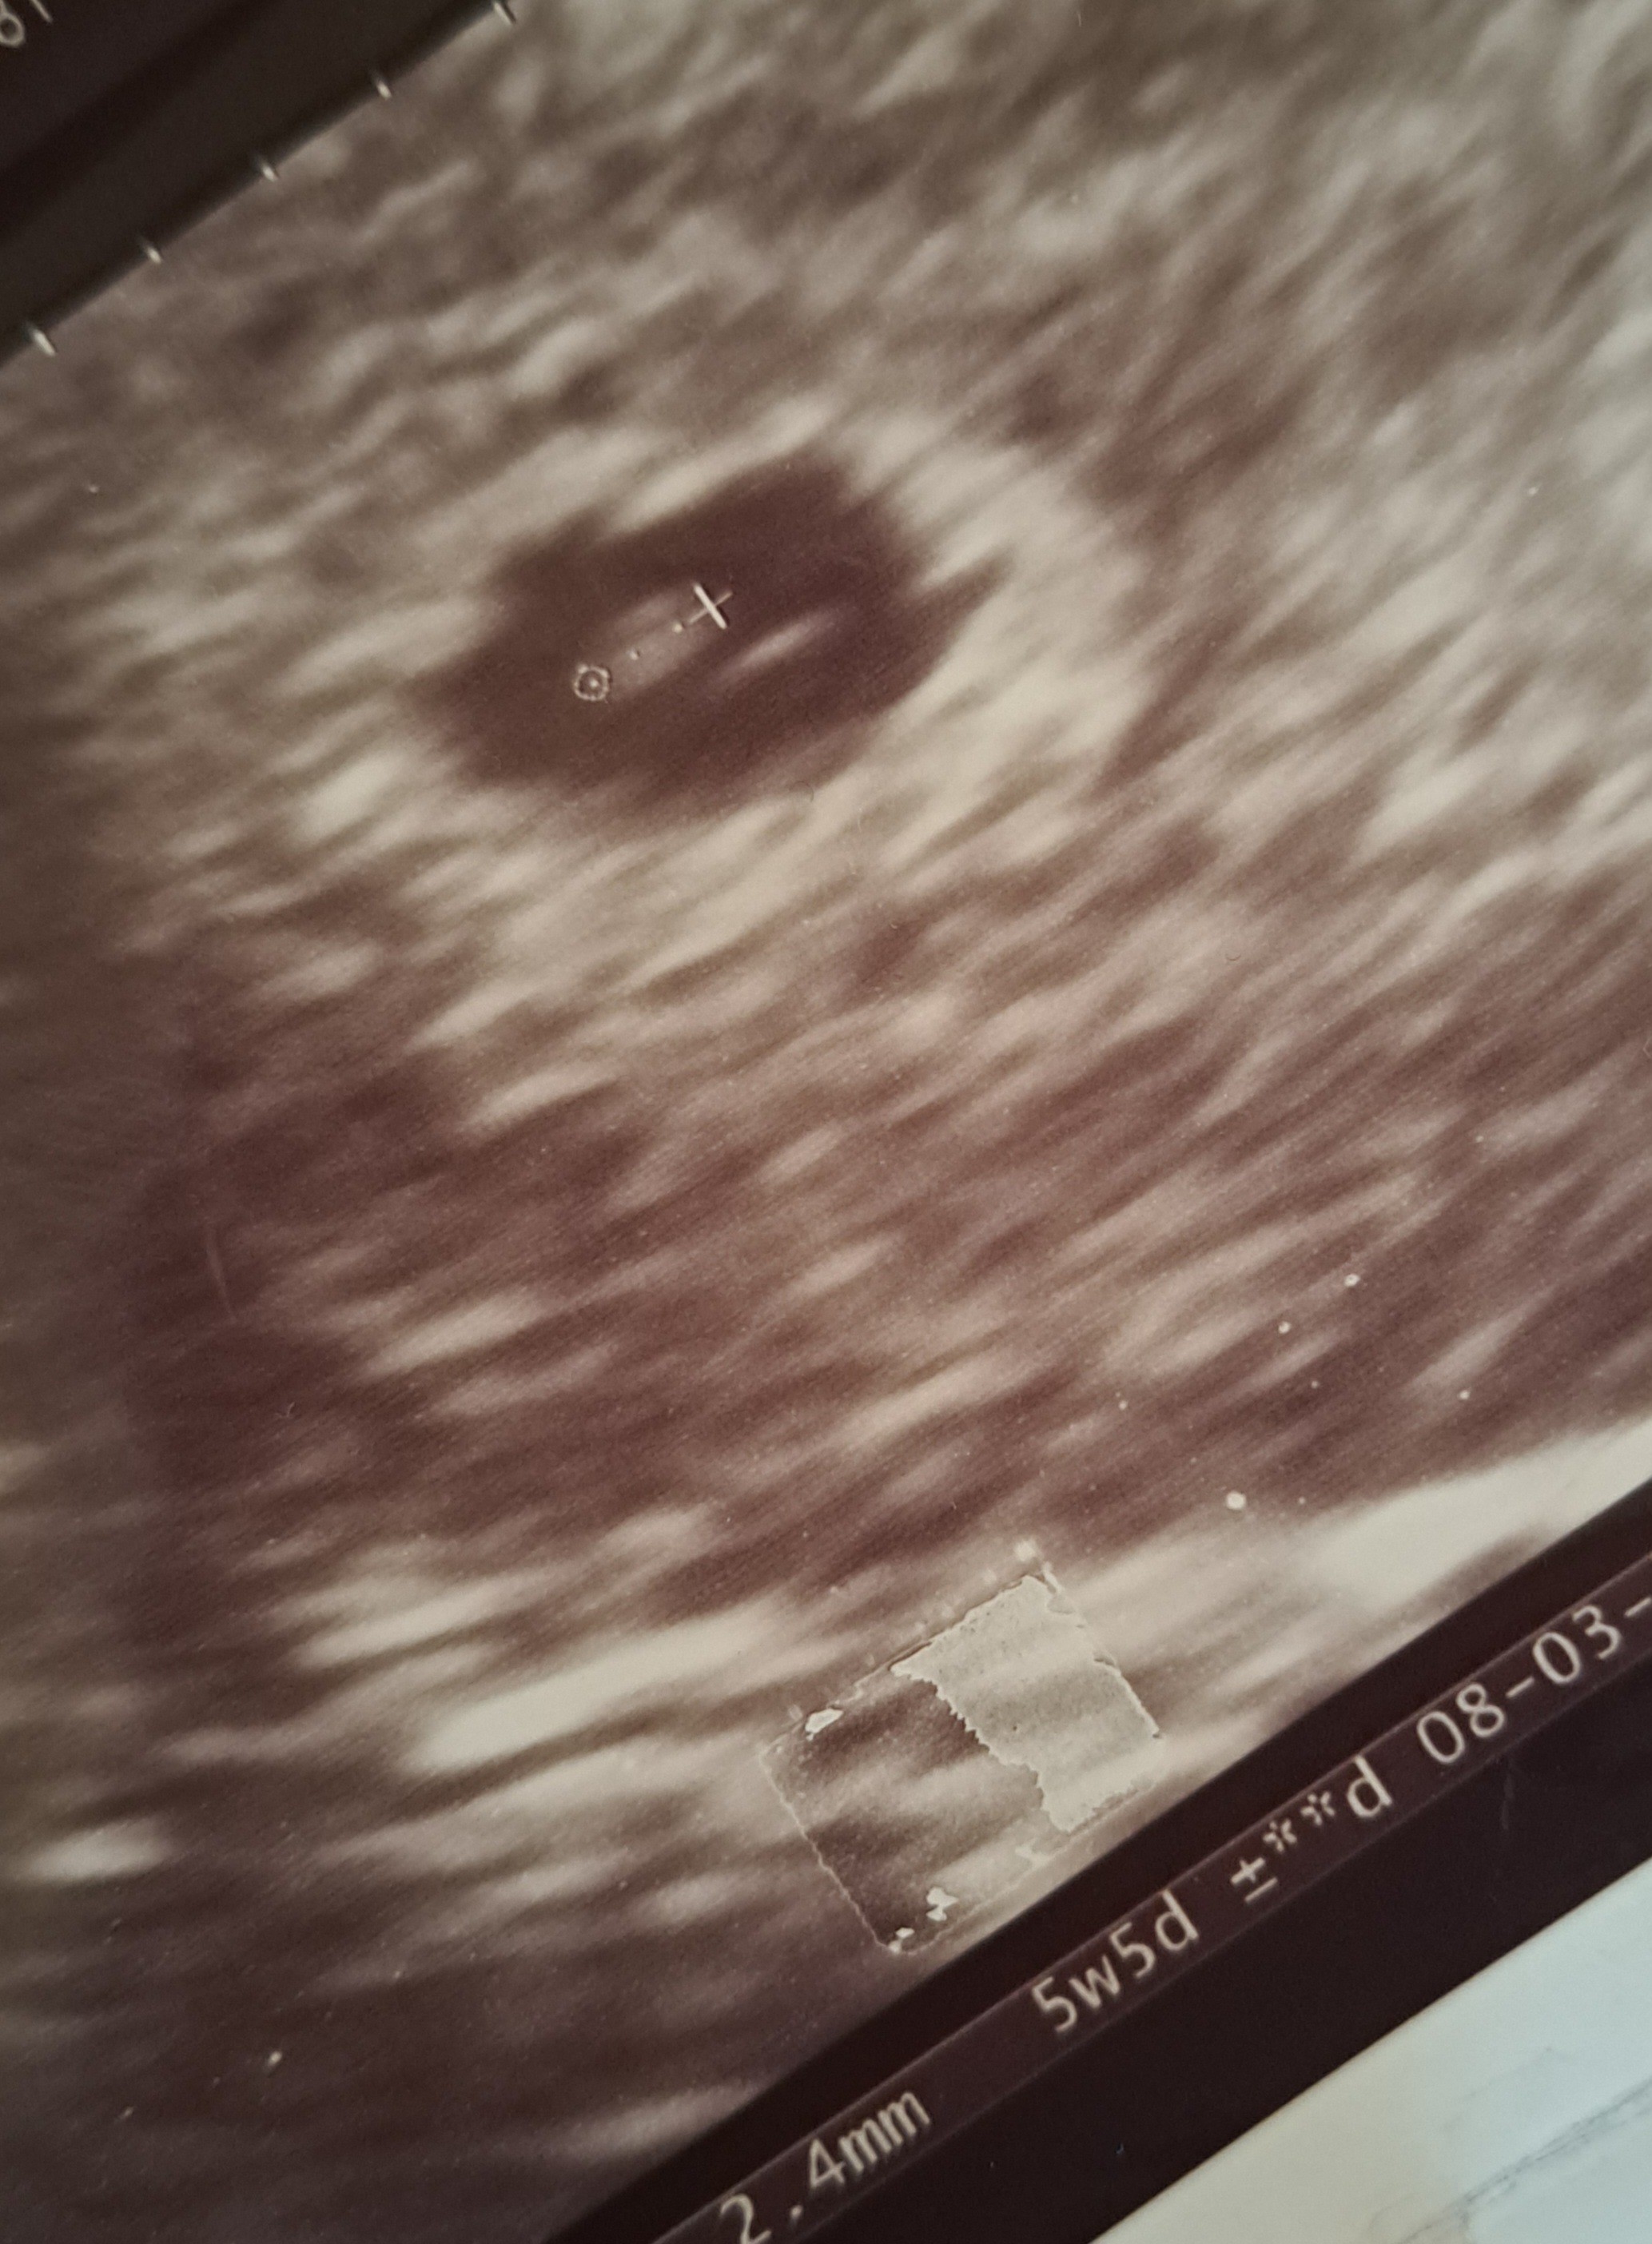

Powiedział że pecherzyk odpowiada 4tydz.+2 dnZobacz załącznik 1547960

A zarodek 5+5 i że pecherzyk trochę maly. Serce bije. Mówił że na tym etapie czasem tak jest i wtedy się wyrównuje ale co mam w głowie to moje. I jak sprawdzałam usg z poprzedniej ciazy to mam zapisane na usg GS 7.3mm odpowiada 5tydz. 0dn.

Także beż sensu że 12mm odpowiada 4+2

Tak wygląda moje usg z zeszłego tygodnia.